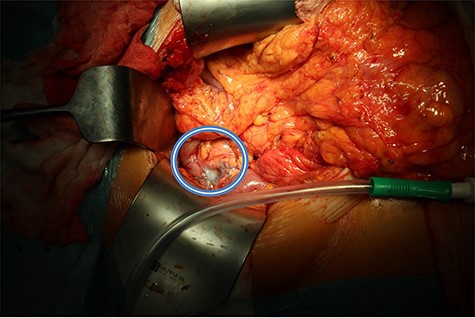

Pancreatic defect after enucleation of insulinoma filled with tissue glue (in the circle).

We present the case of 46-year-old female patient suffering from spontaneous hypoglycemia. She was admitted to our hospital due to worsening clinical symptoms. At first, she underwent a 72-hour monitored fast and biochemical testing for endogenous hyperinsulinism, which proved positive. Once the other causes of spontaneous hypoglycemia were excluded, we started the process of localization of insulinoma. Then the patient underwent endoscopic ultrasonography (EUS) of pancreas with the find of hypoechogenic, well demarcated, hypervascular tumor in the head of pancreas size of 12.4 × 10.5 mm (Fig.1). Computed tomography (CT) examination of abdomen followed up and tumor of pancreatic head, corresponding with the diagnosis of insulinoma, was found (Fig. 2). It was located nearby pancreatic and biliary duct. Because of serious clinical symptoms, an early surgical treatment was indicated. Based on the evaluation of the surgeon to perform the less radical surgery, it was suggested to enucleate the tumor with preoperative stenting of pancreatic and biliary duct. Two days before the surgery, ERCP with insertion of pancreatic and duodenobiliary stent was performed (Fig. 3). With regard to the patient's preference and overweight, laparotomic approach was selected. Determination of the exact position of tumor was difficult, insulinoma was hardly palpable. We used intraoperative ultrasonography to identify the exact location of tumor (Fig. 4). Then the surgeon palpated the inserted stents and the insulinoma was identified intrapancreatically, 3–4 mm nearby pancreatic and bile duct. Enucleation of tumor was performed by harmonic scalpel (Fig. 5). During the surgery, the right position of stents was verified by touch. After enucleation, there was no presence of bleeding, the defect was filled with tissue glue (Fig. 6). Macroscopically, tumor was round shaped, well capsulated, size 1 cm (Fig. 7). During postsurgery period, the patient was stable and with no signs of complication. On the sixth postoperative day, endoscopic removal of pancreatic stent was carried out. Patient was discharged from the hospital on the eight postoperative day. Duodenobiliary stent was left in ductus choledochus for 1 month.